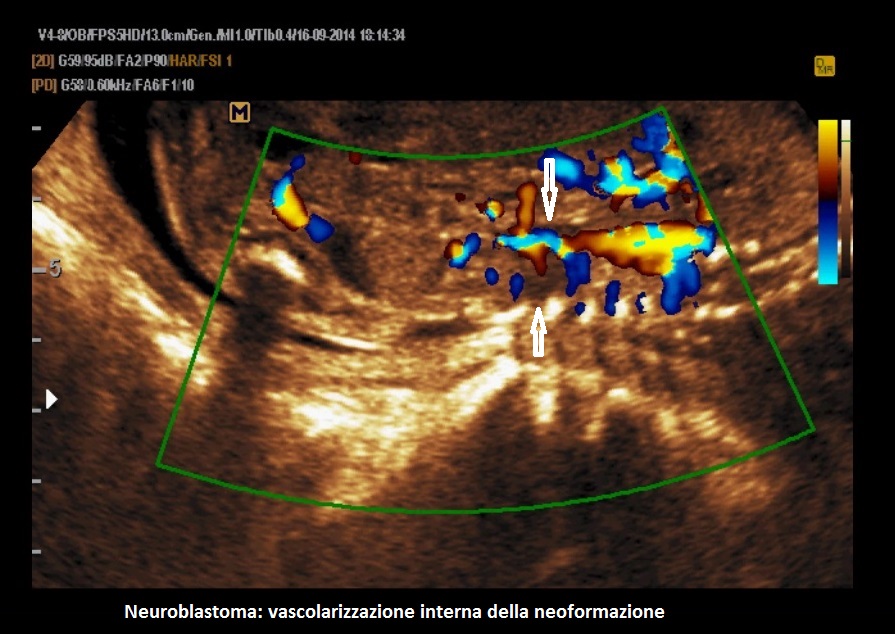

In presenza di una massa del surrene il primo sospetto deve essere orientato verso il neuroblastoma che rappresenta il tumore solido più frequente in età infantile, con una incidenza di circa 1:7000 - 1:10000.  Il tumore può presentarsi come una neoformazione monolaterale o bilaterale, in forma cistica, solida o complessa, riccamente vascolarizzata al Color-Doppler. Può metastatizzare il fegato, provocando epatomegalia, e la placenta provocando placentomegalia; altro segno legato alla metastatizzazione è l'idrope.